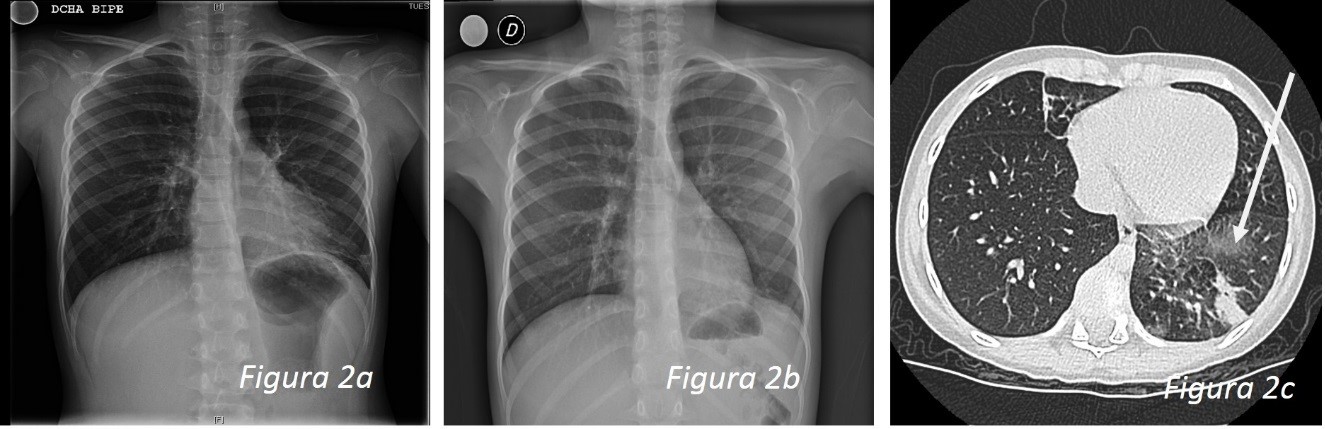

A los 11 años se realiza una radiografía de tórax donde presenta hiperinsuflación generalizada (Fig. 1a), se repite el Mantoux, que vuelve a ser de 0 mm, y se deriva a la consulta de Neumología Infantil, donde se realiza una espirometría con test de broncodilatación positivo, y estudio de alergia positivo a gramíneas, epitelio de gato y ácaros. Se diagnóstica de posible asma episódico ocasional/frecuente.

A los 12 años, ante la persistencia de APP, incluso en visitas por otros motivos, se vuelve a remitir a Neumología, donde se realiza un ionotest, que es normal, y se repite la radiografía de tórax (Fig. 1b): hiperclaridad del pulmón izquierdo con disminución del pedículo vascular, sugestivo de bronquiolitis constrictiva post infecciosa (síndrome de Swyer-James). Se completa con una tomografía computarizada (TC) torácica (Fig. 1c), observándose una disminución de la atenuación del pulmón izquierdo con áreas parcheadas de atrapamiento aéreo en la espiración, y disminución del calibre de la arteria pulmonar central y de las ramas periféricas, sobre todo del lóbulo inferior izquierdo (LII) y morfología bronquial ligeramente irregular en la pirámide basal izquierda sin visualizarse bronquiectasias distales; hallazgos compatibles con bronquiolitis obliterativa (BO) como posible secuela de infecciones en la infancia en el pulmón izquierdo.

| Figura 1. Caso 1: a) hiperinsuflación generalizada; b) hiperclaridad del pulmón izquierdo con disminución del pedículo vascular, sugestivo de bronquiolitis constrictiva posinfecciosa (síndrome de Swyer-James); c) TC: disminución de atenuación del pulmón izquierdo con áreas parcheadas de atrapamiento aéreo en la espiración, una disminución del calibre de la arteria pulmonar central y de las ramas periféricas, sobre todo del LII |